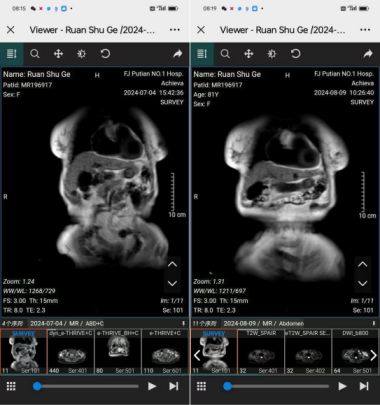

有关医院案例值得心重思考,医院对病人要动手术,病人不同意动手术,保守护健康,提醒大家,我经过病人告诉分享给大家,案例如下:仙游交尾梧店村阮妹哥,80岁,女,于2024年7月2日医院检查,肝硬化腹水,范围约16.5㎜x13.3㎜x13㎜,肝内多发类圆形大者径约15.6㎜,胆囊体积增生,壁稍增厚,胆囊腔内结节长径约10.5㎜,脾脏体积增大,脾内见小结节状,径约10.5㎜,所见双肾多发类园形大者径约20.5㎜,肝硬化并多发再生结节,脾肿大,轻度脂肪肝,胆囊结石伴胆囊炎,肝,双肾多发囊肿。要动手术,患者不同意手术,医生不高兴,变服务态度不好,(这是为什么),于7月10日病人要求出院。经人介绍12日找杨宗仙拿药,肝硬按压疼痛,拍下病人照片为据,7月21月再来拿药病人介绍好转很多,肝按压软轻微痛,身体恢复拍下照片为据,于8月9日到医院复查受到医生打击,服务态度不好,说没有那么快好转,待3亇月来复查,家属要求复查,经复查医生说病状一样没有好转,(这是为什么),家属反问医生母亲身体恢复正常满面风光,感觉凝问,8月15再来找我,据家属反应复查情况等事。我发现7月3日报告单写患者80岁,报告单医生与审核医师各人签字,8月9日复查报告单写患者81岁,一个月增加1岁,增创世界12亇月加12岁,报告医生与审核医师同一亇人签字,复查报告单与7月3日核对病状一致一字不差,根据7月4日肝图片和8月9日复查肝图片对比基本恢复正常。